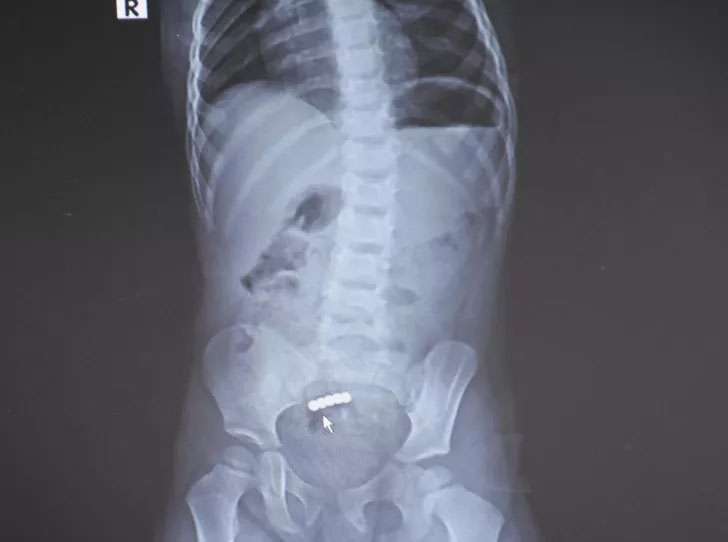

Küçük kızın bağırsağından çıkanlar şaşkına çevirdi.

“EVLERİNE SOKMAMALARINI ÖNERİYORUZ” Gerekirse bu gibi oyuncakları evlerine sokmamaları gerektiğinin altını çizen Dr. Özkaya, şöyle devam etti: “Bu vesileyle de ailelerimizi uyarmak ve bilinçlendirmek istiyoruz. Ailelerin özellikle bu tarz renkli küçük mıknatısların çocuklardan uzak tutulmasını öneriyoruz. Renkli küçük mıknatıslar çocuklara daha cazip geliyor ve yutabiliyorlar o yüzden bu tarz oyuncakları çocuklarda uzak tutmaları ve hatta gerekirse evlerine sokmamalarını öneriyoruz.” Çıkartılan mıknatısları yaklaşık 1 yıl önce yutulduğuna dikkati çeken Dr Özkaya, “Bu mıknatısların bir yıl gibi bir süredir yuttuğunu düşünüyoruz. Çünkü bu mıknatısların artık renkleri de değişmiş durumda ve paslanmış durumda. O yüzden de bir yıldır ara ara karın ağrısı çekiyormuş. Bunlar renkli renkli ve kuvvetli mıknatıslar” ifadelerini kullandı. Yoğun karın ağrısı şikayetiyle kızını hastaneye götürdüğünü belirten baba Servet Altundağ ise, “Karın ağrısından dolayı acile gittik. Şırnak’ta doktorlar Batman Eğitim ve Araştırma Hastanesine sevk ettiler. Yabancı cisim yuttuğundan dolayı orada bir şey yapamadıklarını söylediler buraya sevk ettiler. Çok şükür burada şifamızı bulduk, Selim hoca ve ekibine teşekkür ediyorum. Ailelerden böyle cisimleri çocuklarından uzak tutmalarını öneriyorum, bizim başımıza geldi başkalarının başına da gelmesin” dedi.